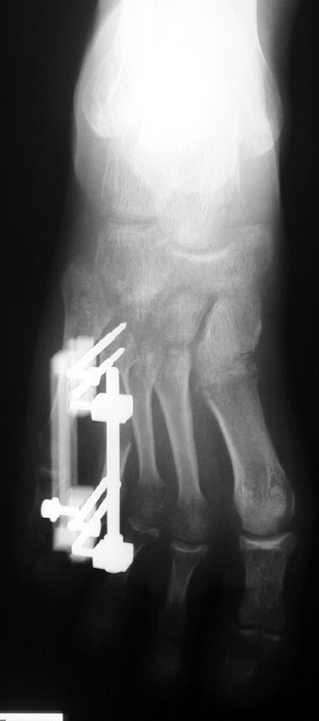

Doğuştan metakarp ve metatars kısalıklarının redavisi için pek çok teknik tanımlanmakla birlikte en çok akut uzatma sonrası kemik uçlarına greft konması ve distraksiyon osteogenezi (kallotasis) kullanılmaktadır. 1 cm.den daha fazla uzatma gereken olgularda kallotasis yöntemi önerilmektedir. Kliniğimizde de metatars ve metakarp uzatma için unilateral eksternal fiksatör ve sirküler eksternal fiksatör yardımıyla distraksiyon osteogenezi yöntemi tercih edilmektedir.

Vaka 1